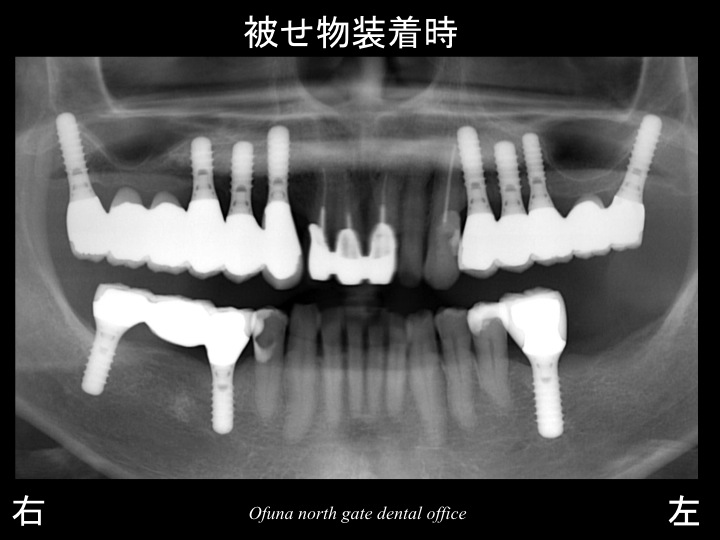

以下は、インプラント治療が終了した状態です。

使用したインプラントは、

アンキロス インプラント と

ストローマンインプラント(ITIインプラント)

です。